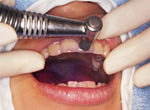

3.研磨剤を注入

歯と歯の間、歯の付け根に研磨剤をつけていきます

4.歯科用専用器具で磨く

歯と歯の間の汚れをていねいに落としていきます。

この器具は患者さまの衛生管理のため全てデイスポーザブル(使い捨て)にしています。